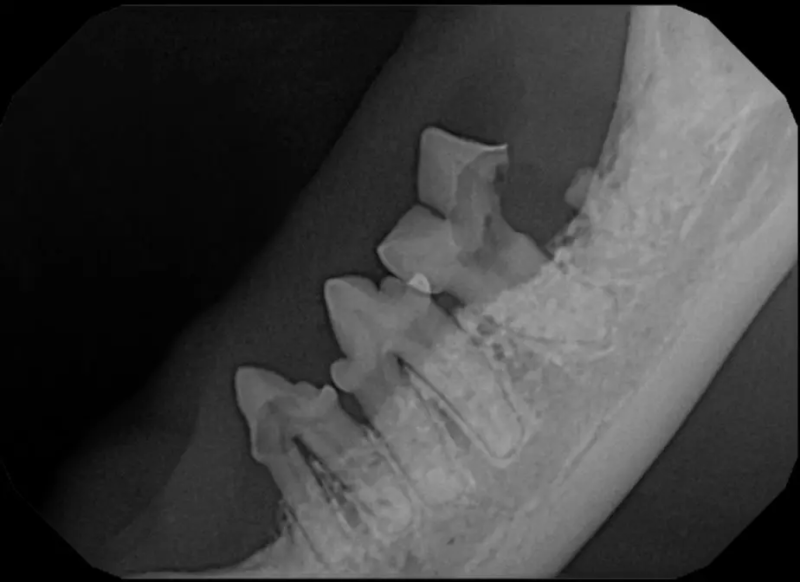

Tooth Resorption

Tooth resorption is a disease process where the body begins to break down the adult tooth. It is widely known to occur in cats but can also occur in dogs. In cats these lesions are thought to be inflammatory, while in dogs they can be more of a replacement resorption process. These lesions can be very painful and should be treated, generally with extraction depending on the type of resorption that is occurring. The disease can be progressive and affect many teeth over several years. It is important to have regular checkups and yearly dental cleanings to monitor for these lesions.